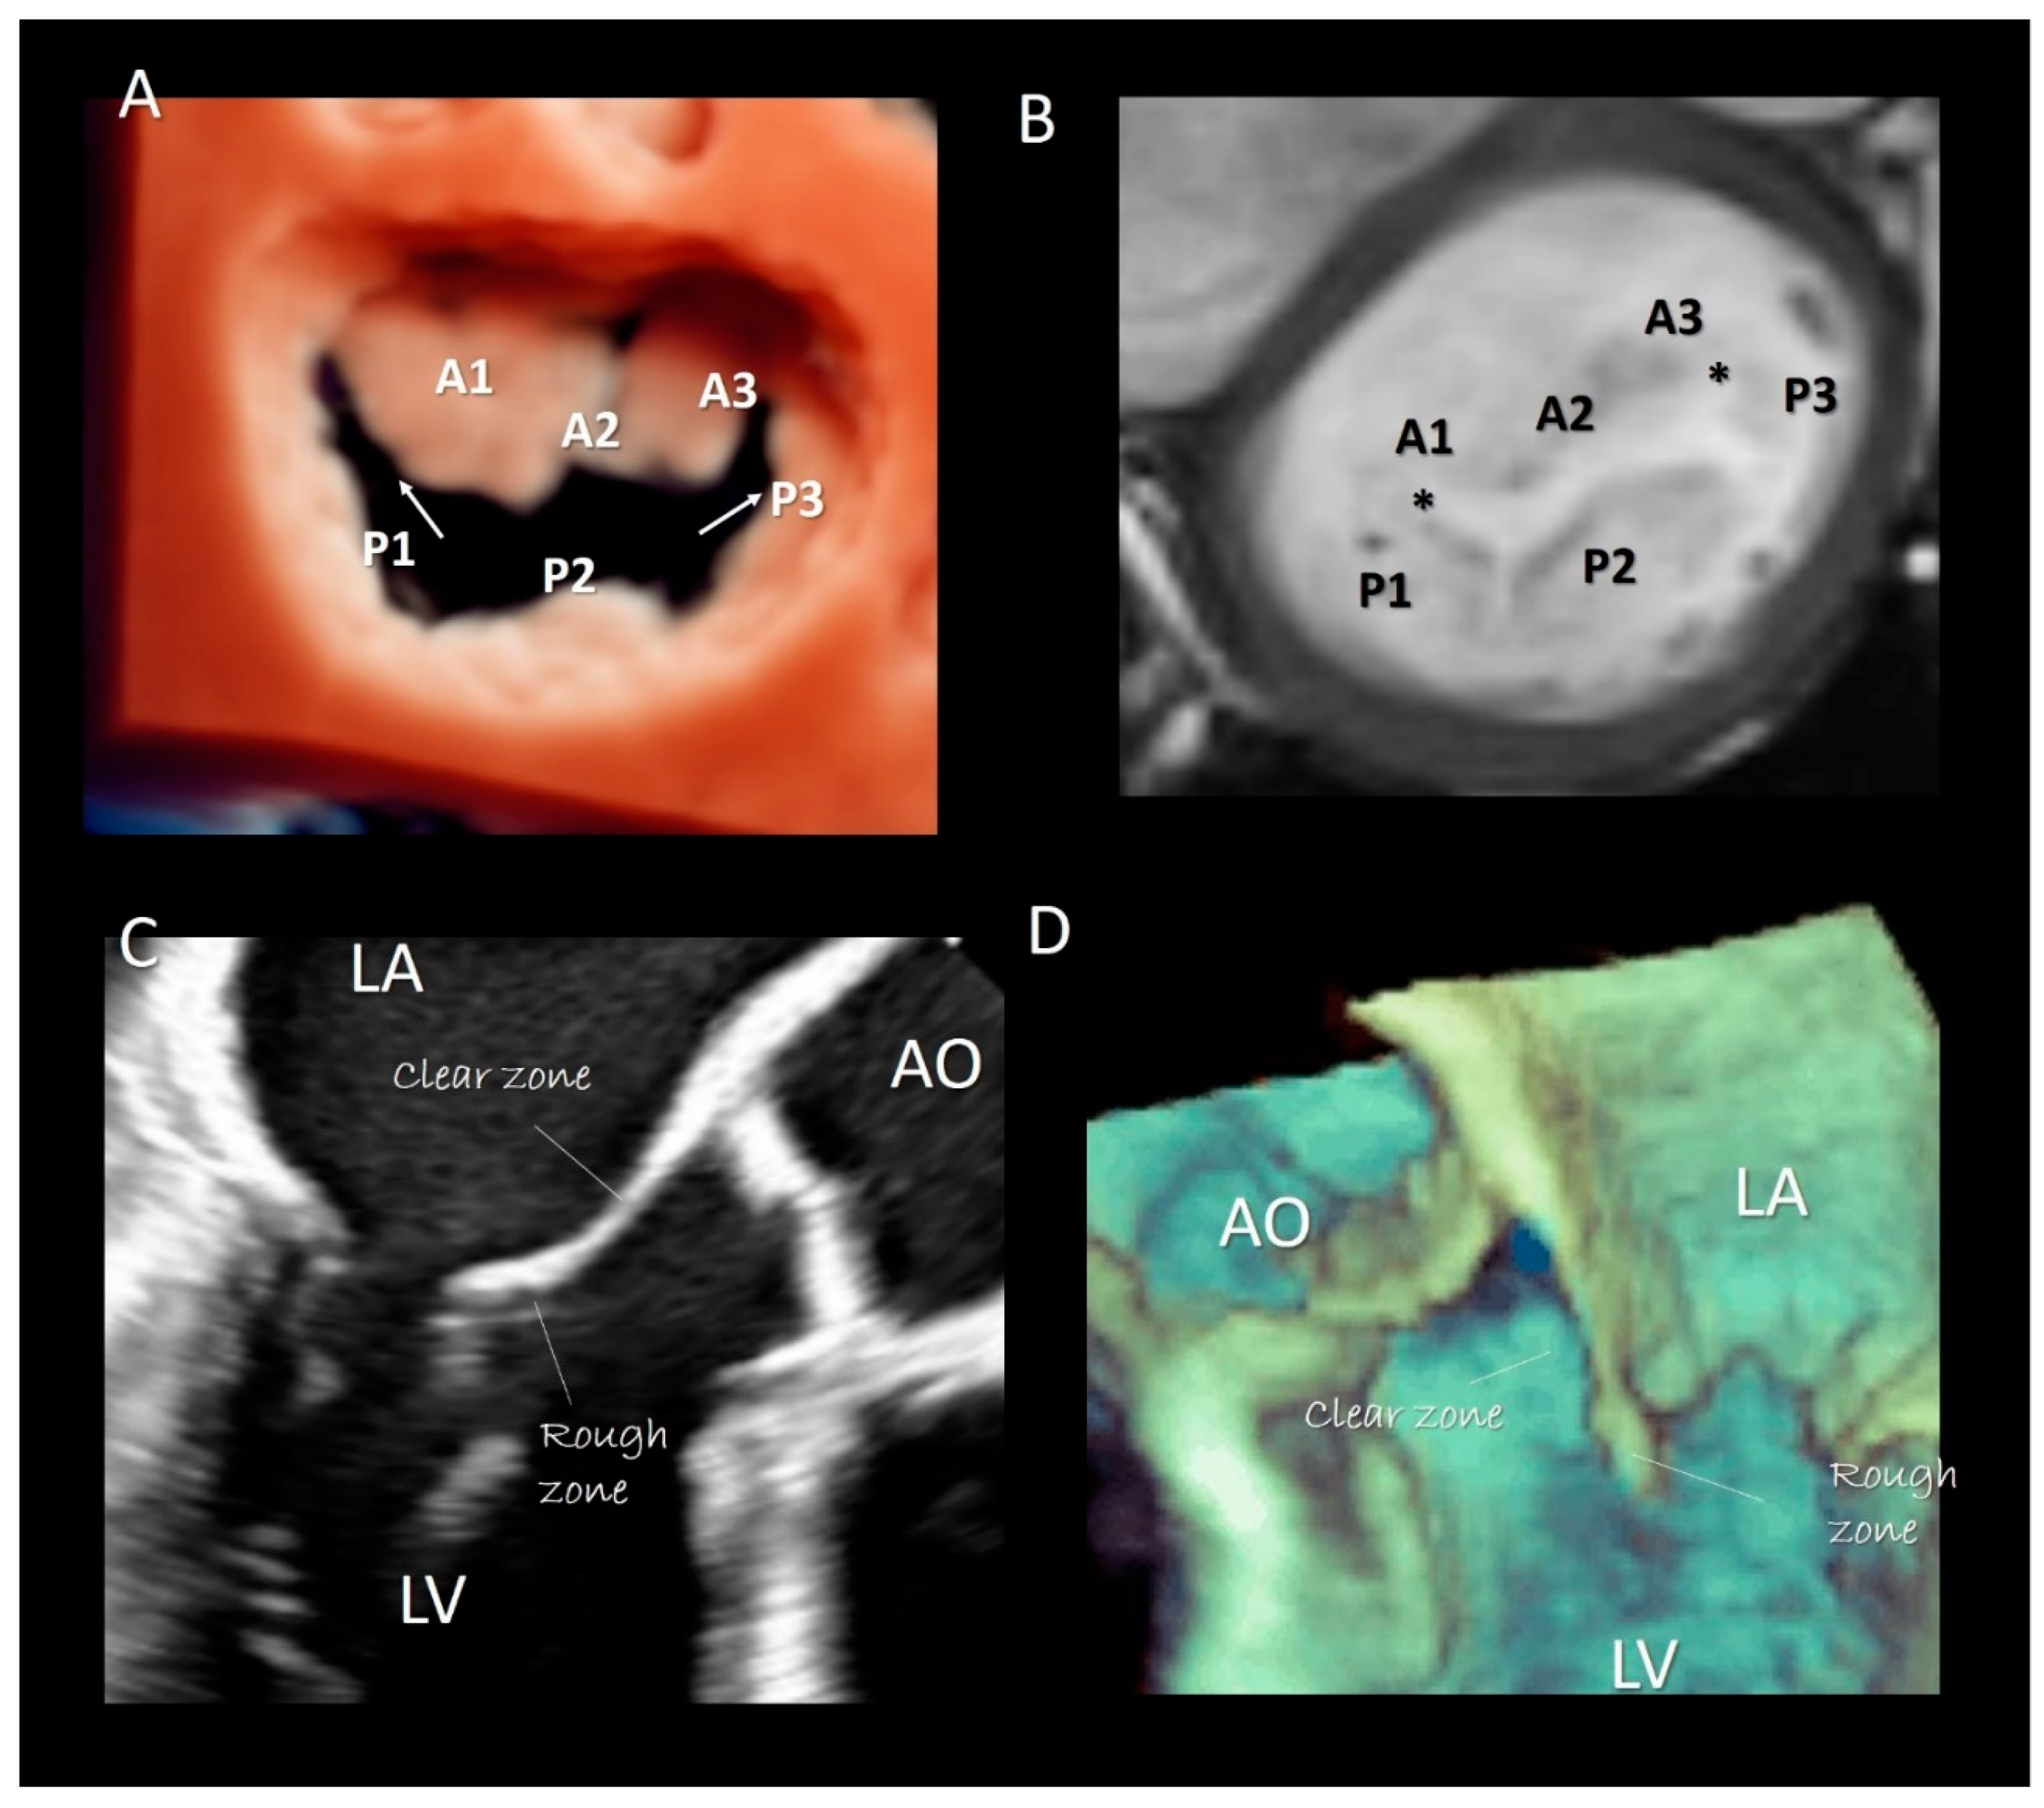

Two deep commissures separate the mitral veil in two halves. The anterior (or aortic) mitral leaflet (AML) and the posterior (or mural) mitral leaflet (PML). At both ends of the zones of apposition between the aortic and mural leaflets can often be found commissural leaflets, which occasionally can be extensive. The AML has an almost triangular-shaped surface and its hinge line covers approximately 1/3 of the annular circumference. The posterior leaflet has a more rectangular-shaped surface and its hinge line covers the remaining 2/3. As the AML is longer than the PML, the area of the two surfaces is equal. In the majority of normal MV, the PML is divided by two incisures into three parts, called scallops: P1 (lateral), P2 (central), P3 (medial). Conversely, the anterior leaflet has no identifiable incisures. However, surgeons call the areas of the AML opposing the corresponding scallops of the posterior leaflet A1, A2, and A3, (Figure 5A,B). Inspection of the ventricular surface of both leaflets reveals two distinct areas: the rough and clear zones. The rough zone receives the insertion of chordae tendineae and presents a “corrugate” and thicker aspect, while the clear zone, lacking chordal insertion, has a smoother, thinner and sometimes translucent appearance (Figure 5C,D). Interestingly the rough zones correspond on their atrial aspect to the area where leaflets juxtapose each other during the systole. The vast majority of chordal attachment is therefore within the coaptation area sharing the mechanical stress with the leaflets. Lack of coaptation between leaflets causes not only a mitral regurgitation but also an abnormal traction on chordae tendineae with an increasing risk of chordal rupture.

Figure 5.

(A) 3D TEE with a new volume rendering algorithm from an overhead view, showing the two commissure (arrows) and the P1, P2, P3 scallops of the posterior leaflet. A1, A2, A3 are the corresponding segments of anterior leaflet. (B) CMR cross-section short-axis at the level of mitral leaflets showing the commissures (asterisks) and the scallops. (C) 2D TEE and (D) 3D TEE cross-section long-axis views showing the rough and clear zones.

Though in recent years CMR and CT have been increasingly used for evaluating MV apparatus, especially in the pre-operative or pre-interventional setting [19,21], there is no doubt that 2D/3D TEEs are probably the best modalities for visualizing mitral leaflets. Remarkably, once acquired, 3D volumetric data set can be rotated and angulated, allowing visualization of leaflets in a countless number of perspectives. There are at least four 3D TEE “basic” perspectives that are clinically useful: the perspective from overhead, also called “surgical view”, which provides images of leaflets equal to the surgical inspection in the operating room, the perspective from left ventricle which provides images of ventricular surface of the leaflets, the angled right-to-left and left-to-right perspectives which allow a better vision of medial and lateral commissures [22] (Figure 6). Moreover, slight angulations or rotations from these basic perspectives or selective cropping permits visualizing anatomic details of the leaflets.